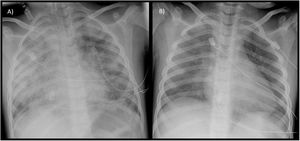

A female patient aged 5 years with a history of recurrent bilateral pneumonia presented with acute respiratory failure, bilateral pulmonary infiltrates and microcytic anemia (hemoglobin [Hb], 9.7 g/dL; mean corpuscular volume [MCV], 67 fL). She was admitted to the pediatric intensive care unit (PICU), where she underwent placement of a central jugular catheter, a urinary catheter and a size 5 tracheal tube for mechanical ventilation. The presence of blood in the secretions suctioned through the tracheal tube prompted performance of flexible bronchoscopy with bronchoalveolar lavage (BAL), with a hemosiderin-laden macrophage percentage of 80% of in the cytological analysis. The patient was treated with intravenous steroids, which achieved resolution of symptoms and normalization of the chest radiography features within 48 h (Fig. 1). In the months following diagnosis, the management consisted of intravenous maintenance boluses of high-dose methylprednisolone, oral hydroxychloroquine and inhaled budesonide. Since the patient developed Perthes disease secondary to steroid therapy and experienced exacerbations upon attempting to taper or discontinue it, oral azathioprine was added on stopping steroid therapy, with a favorable response to date.